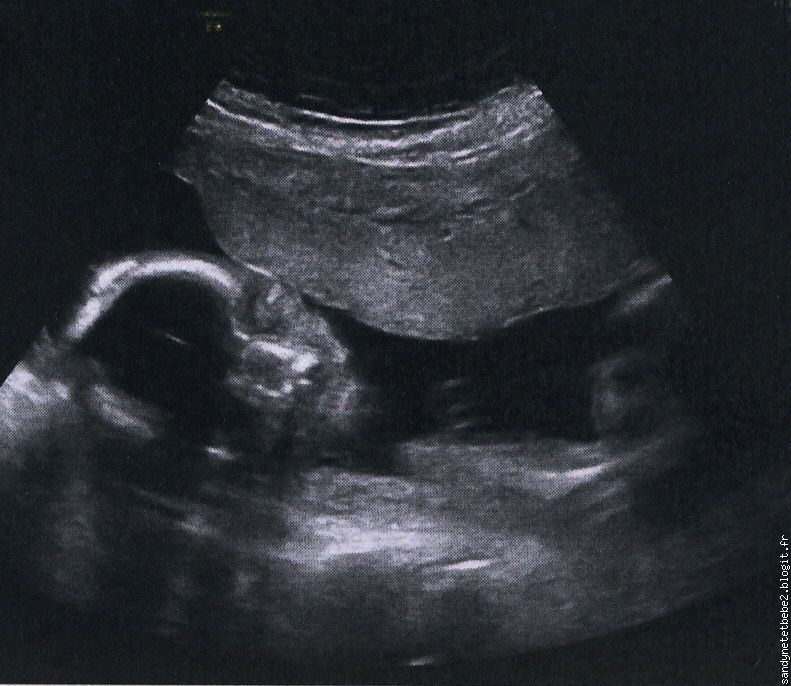

2ème échographie

| écho2 bébé2 |

Lundi 12 juillet 2010 :

Enfin la deuxième écho de bébé et enfin je vais connaitre le sexe de bébé.

Juste pour dire que l’écho s’est bien passée, que tout va bien, bébé se porte bien et c’est ça le principal à retenir.